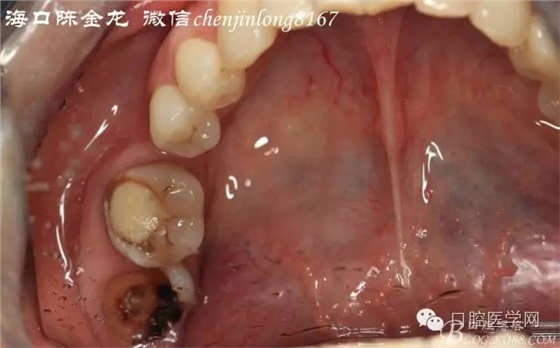

右下8被移植牙

右下8形態(tài)

后期主要注意三個方面:

第一牙髓情況

第二牙周膜連續(xù)情況

第三根尖吸收情況

種植成功后觀察是否需要根管治療,后期通過正畸方法關閉右下6的拔牙間隙。